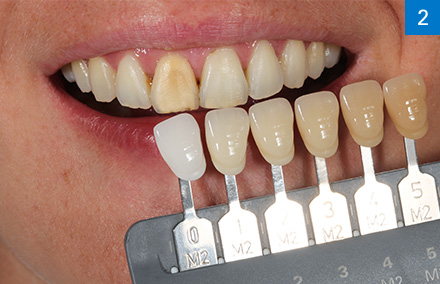

Taïwan : Cas VITABLOCS du Dr Mon Li et de la prothésiste dentaire Sally Hsieh

Dr. Mon Li et Prothésiste dentaire Sally Hsieh, CEREC Asie, Taipei, Taïwan

« Le dégradé de couleurs intégré en quatre couches d’intensité permet un jeu de couleurs et de lumière naturel dans la zone esthétique. »

Une histoire à succès : Reconstitution vivante de dents antérieures en céramique feldspathique polychrome

Situation initiale

Après un traitement radiculaire, une patiente de 20 ans n’était pas satisfaite de la coloration foncée de la 11, qui ne présentait par ailleurs aucun symptôme. La radiographie a montré une obturation radiculaire suffisante.

Solution

Après consultation approfondie, la patiente a choisi une restauration rapide par couronne en tout céramique à base de céramique feldspathique polychrome VITABLOCS TriLuxe forte afin de stabiliser la 11 à long terme et de répondre à ses attentes esthétiques. La morphologie originale devait être conservée et a donc été scannée avant la préparation pour la conception de la couronne. La détermination précise de la couleur de la dent adjacente a été réalisée avec le VITA Easyshade V afin de pouvoir choisir le bloc adéquat.

Pourquoi VITABLOCS TriLuxe forte ?

Nous avons utilisé VITABLOCS TriLuxe forte car la patiente souhaitait une restauration coronaire hautement esthétique et définitive en une seule séance dans la zone esthétique. Grâce au dégradé de couleur intégré et au brillant jeu de couleurs et de lumière du bloc de céramique feldspathique polychrome, nous avons pu obtenir le résultat souhaité avec un minimum de caractérisations, malgré le petit corridor temporel.

Le spectrophotomètre VITA Easyshade V a permis de déterminer avec précision la couleur de la dent.

La couleur de dent 2M1 déterminée numériquement a été documentée à l’aide de la barrette de couleur échantillon correspondante.